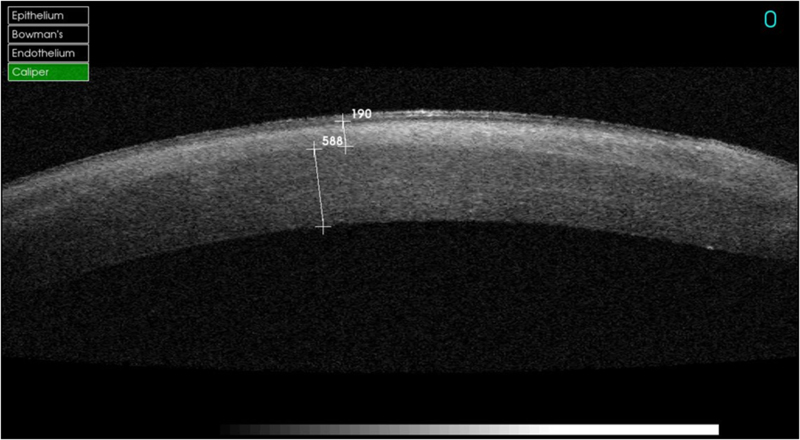

Figura 1). También se pueden estudiar adelgazamientos corneales como el queratocono (

Figura 2), opacidades corneales estromales y su profundidad, patologías asociadas al LASIK (

Figura 2. Vemos la ectasia de un queratocono.

Figura 3. Infección en operado de LASIK.